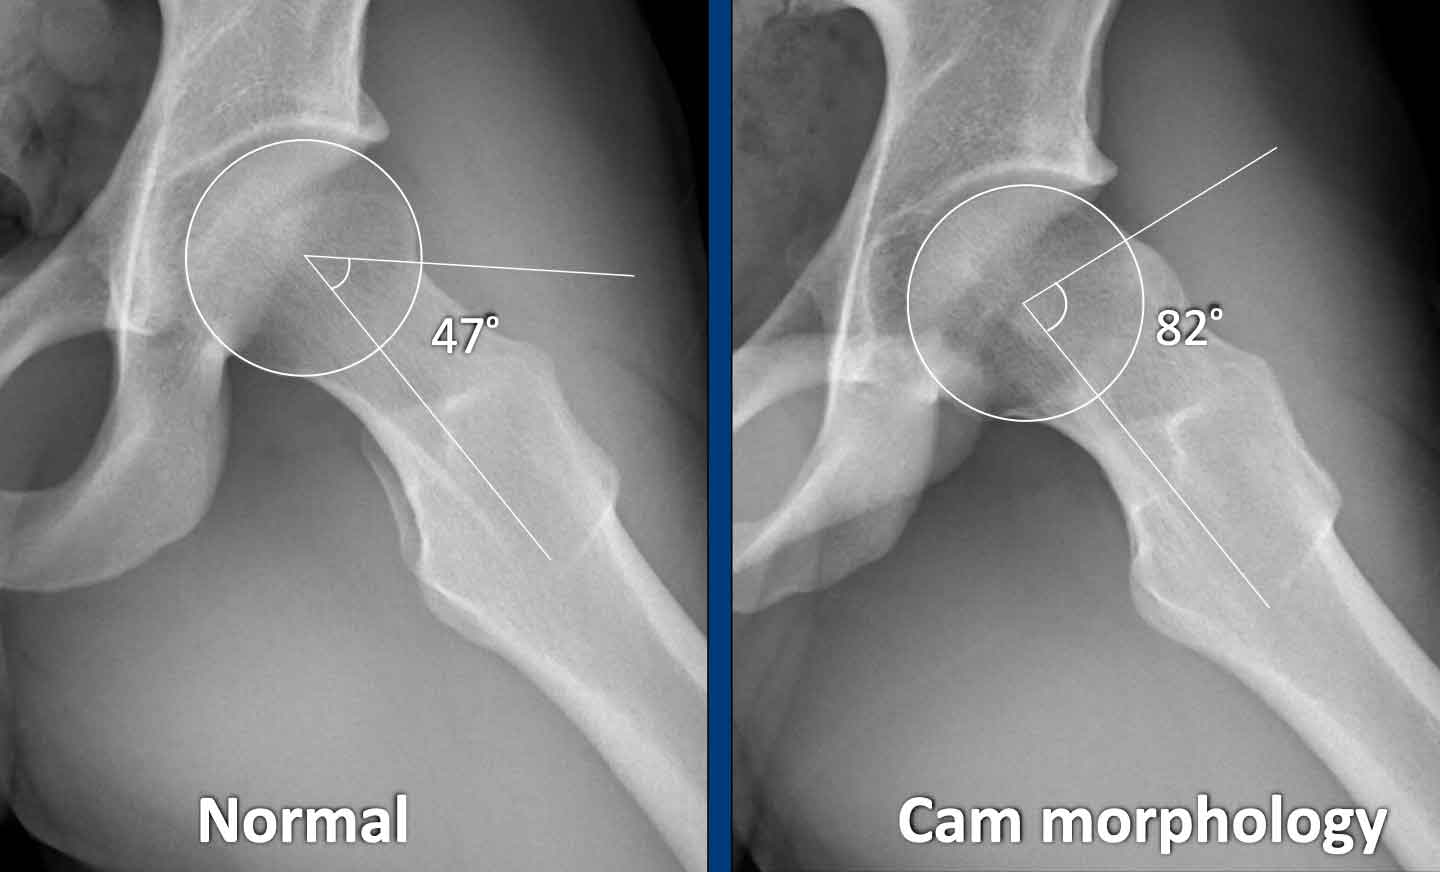

Góc alpha

Góc

alpha được đo bằng cách vẽ một đường tròn qua chỏm xương đùi, một đường thẳng

từ tâm cổ xương đùi đến tâm chỏm xương đùi, và sau đó

một đường thẳng từ tâm chỏm xương đùi đến điểm giao nhau giữa chỗ nối chỏm-cổ xương đùi với đường tròn.

Nếu góc từ 60 độ trở lên, có thể được phân loại là hình thái Cam.

Phép đo này có thể được sử dụng trên cả hình ảnh thông thường lẫn

hình ảnh cắt lớp – trong đó hình ảnh cắt lớp có độ nhạy cao hơn.

Ngưỡng giá trị gần đây đã được tăng lên 60 độ để tăng tính đặc hiệu.

Alpha angle measurement

Hông bình thường có góc alpha nhỏ hơn 60º.

Hông có hình thái Cam có góc alpha lớn hơn 60º.

Tất nhiên, khi hình thái Cam rõ ràng như trong trường hợp này, các

phép đo này là không cần thiết trong thực hành lâm sàng.